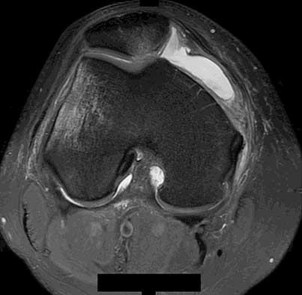

Surgical repair of the injury shown in the MRI scans in Figures 1 through 4 through a single-incision approach has a higher incidence of

The MRI scans show a distal biceps tendon avulsion with significant retraction. When addressing these injuries, a single-incision approach has been associated with an increased risk of lateral antebrachial cutaneous nerve injury. A two-incision approach has been associated with an increased risk of heterotopic ossification, second surgeries and posterior interosseous nerve injury.